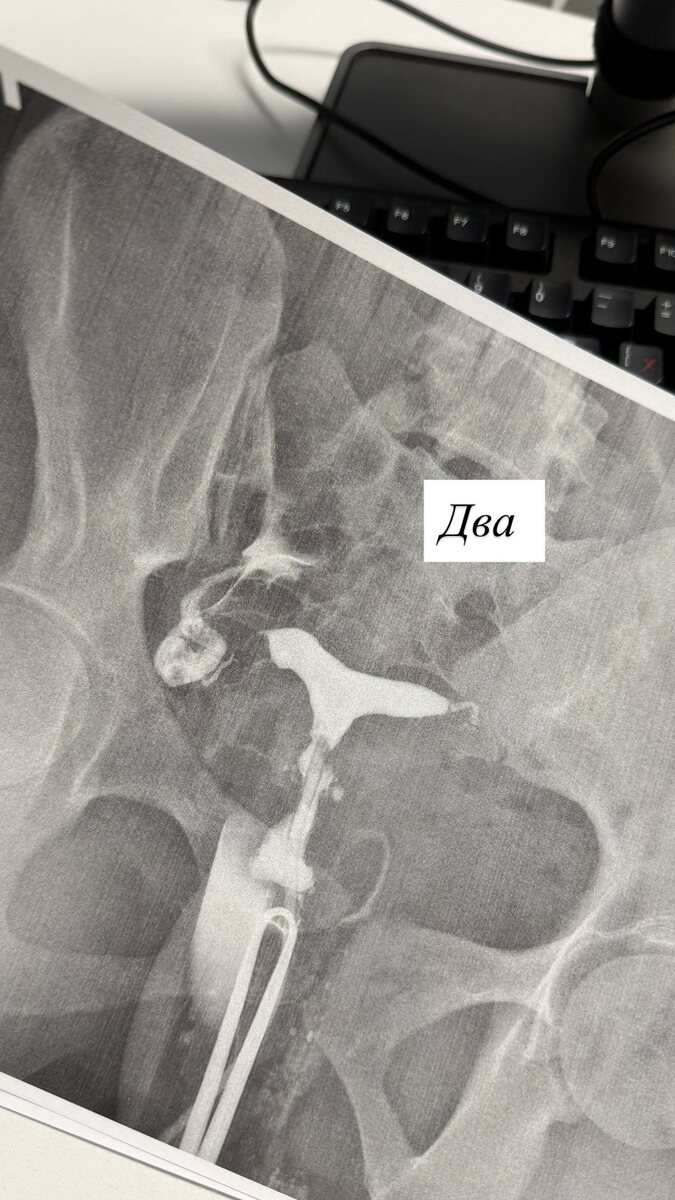

Молодая девушка 28 лет , в анамнезе - две операции по поводу кист яичников , сейчас признаки спаечного процесса в брюшной полости и безуспешные попытки к 🤰

Посмотрели сегодня проходимость маточных труб . Слева - не проходимо , спайки все замуровали. Слева - на серии первых снимков - глухо, потом я максимально «перекрестом» зафиксировала пулевыми щипцами цервикальный канал и под давлением ввела контрастное вещество. И ура - слева « восстановили» проходимость ! Выход контрастного вещества в малый таз 💫🔥 а значит маточная труба проходима !

Сейчас план - планирование беременности в естественном цикле , будем ловить овуляцию слева ☘️